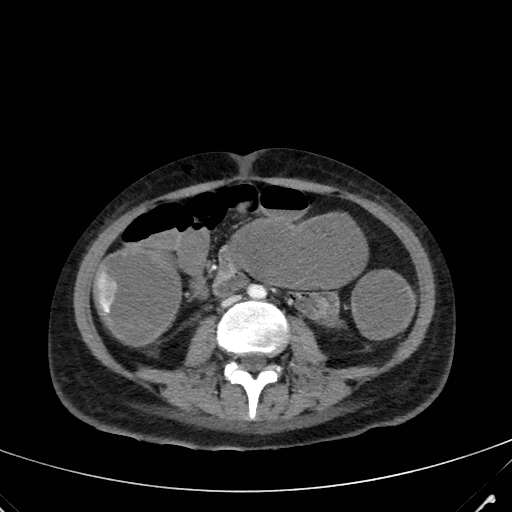

An Eosinophilic Pneumonia Mimicking Lung Cancer on Multiple Imaging Modalities Monitored By CT

Filippo Montella, Ghassan Merkabaoui, Antonietta Vitale, Guido Faggian, Serena De Luca

1-9

PDF